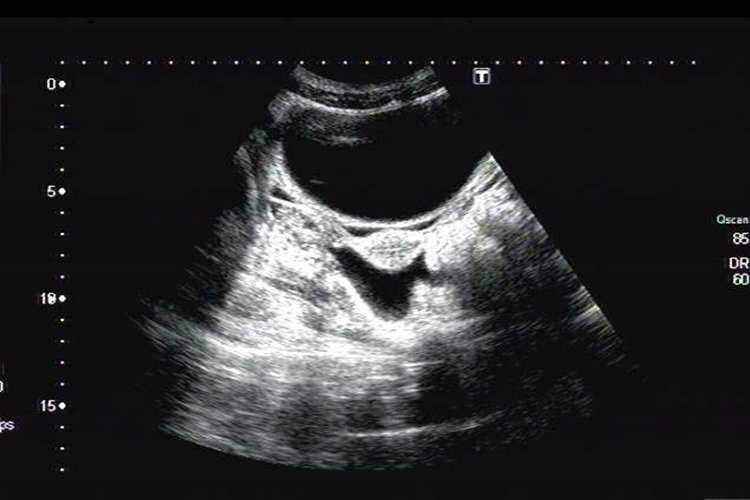

1、生理性盆腔积液:根据患者临床表现,影像学检查CT、MRI表现为水样密度/信号量较少,排卵后液体较多,盆腔各器官均无异常改变,可明确诊断。

2、病理性盆腔积液:根据患者临床表现,出现下腹痛、腰骶痛,腰酸等。影像学检查病理性盆腔积液量较生理性盆腔积液多,少量时多位于病变周围或包裹于某部位,液体因含成分不同,CT密度或MRI信号可有不同,同时可见腹膜和盆腔脏器病变,可明确诊断。